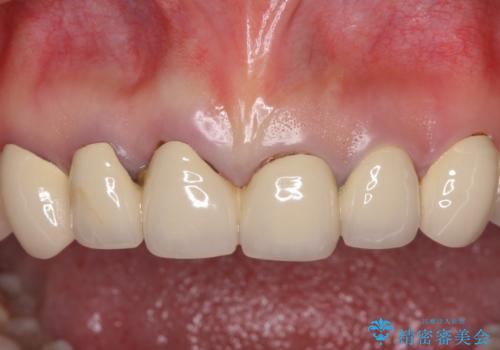

- 前歯のセラミッククラウンの不自然な色調と、虫歯を気にして来院された患者様です。

6歯全てが連結されていたため、外れかけていた右の犬歯は知らぬ間に虫歯が深くにまで進行していました。

深い虫歯の犬歯は、根管治療を行った後に部分矯正を行い、歯周外科処置により環境を整えてから、6歯それぞれのオールセラミッククラウンにて補綴することとしました。